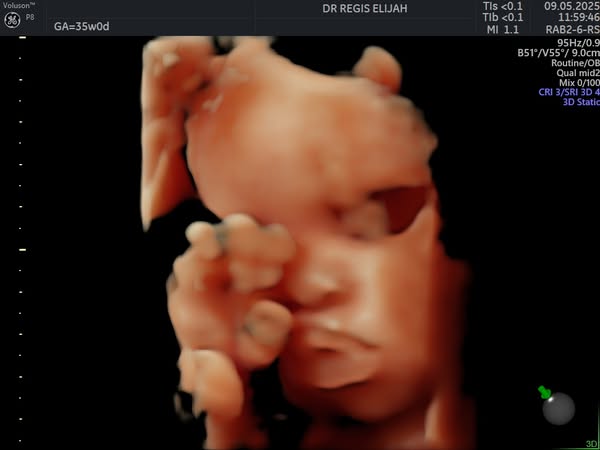

There’s nothing more magical than seeing your baby for the first time—and with our advanced 4D ultrasound technology, you don’t have to wait until delivery day to witness those precious moments!

At Elijah R OBGYN Women’s Clinic, our 4D pregnancy scans allow expectant parents to view their baby’s movements, facial expressions, and little kicks in real time, creating a powerful bonding experience.

🔸 Capture beautiful real-time images

🔸 Detect and monitor fetal development